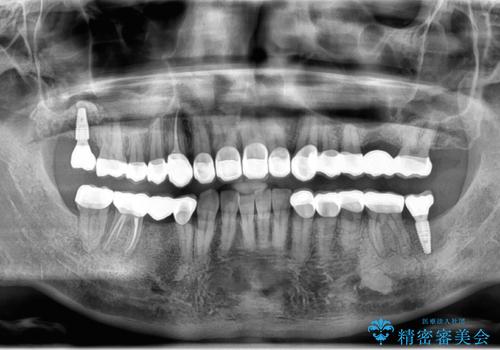

適合の良い被せ物、インプラントが入りました。

全ての治療が終わった後はNG(ナイトガード)を使用し、定期的にメンテナンスに

くることをお勧めしたいます。